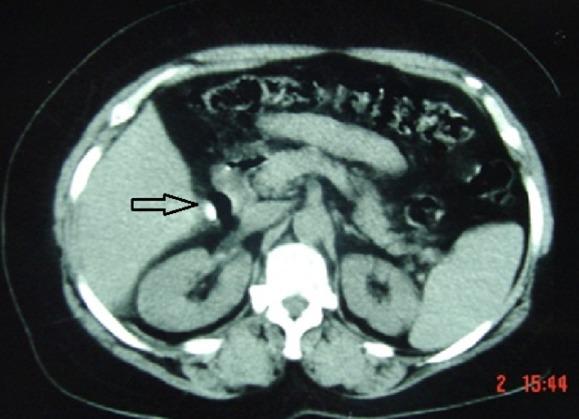

Gallbladder agenesis is a rare congenital anomaly. This study aimed to highlight the epidemiological aspects of this condition as well as the peculiarities of its diagnostic and therapeutic management through three case reports. Two adults were admitted to Hospital with hepatic colics and dyspepsia. Ultrasound showed multilithiasic scleroatrophic vesicle. In one of the two patients, CT scan results showed a stone at the level of scleroatrophic vesicle. These two patients were wrongly operated for vesicular lithiasis by using conventional method. The absence of gallbladder was detected during surgery. In order to confirm post-operative diagnosis, the first patient underwent biliary MRI. The other patient was lost to follow-up. The third patient was a 13-year old child hospitalized with acute pancreatitis. Vesicular agenesis was suspected based on its scannographic aspect and then confirmed using biliary MRI. This patient didn't underwent surgery.

胆囊缺如是一种罕见的先天性异常。本研究旨在通过三例病例报告强调该病症的流行病学方面及其诊断和治疗管理的特点。两名成年人因肝绞痛和消化不良入院。超声显示为多发结石性硬化萎缩性胆囊。在这两名患者中的一名,CT扫描结果显示硬化萎缩性胆囊处有结石。这两名患者通过传统方法被误诊为胆囊结石并接受了手术。手术中发现胆囊缺失。为了确诊术后诊断,第一名患者接受了胆道MRI检查。另一名患者失访。第三名患者是一名13岁儿童,因急性胰腺炎住院。根据扫描图像怀疑胆囊缺如,随后通过胆道MRI得以确诊。该患者未接受手术。